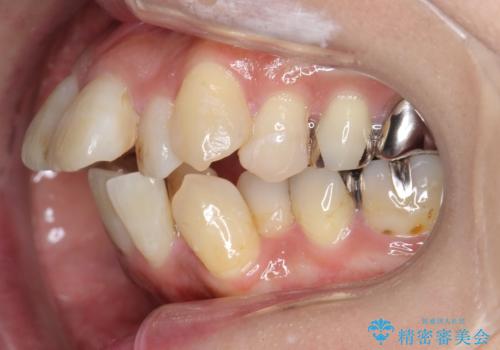

出っ歯 前歯のがたがた 口元を引っ込めたい

- 前歯のがたがた、出っ歯を主訴に来院。

がたつきは中等度で、上の前歯を下げるには歯を抜いてもスペースが不足していた為、上の奥歯を後ろに下げました。

下も混雑が激しく、歯を抜いてもスペースが不足していた為、下の前歯を少し削って小さくして並べています。

歯の移動量が大きく、また、少し歯も動きにくかったため矯正治療に時間はかかりましたがしっかり並べて前突感も大きく改善しました。